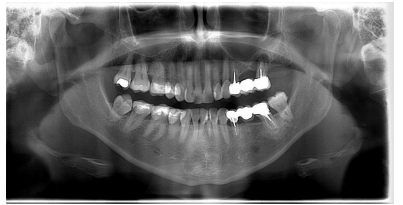

Se solicitó una radiografía panorámica con fines diagnósticos, evidenciándose la presencia de dos imágenes radiotransparentes, a nivel de 31 y sobre el 26. Sobre este último, se observó una lesión apical radiotransparente de forma ovalada de un tamaño de 10,68 mm de anchura y 9,80 mm de altura con límites bien definidos y contorno regular (Figura 1).